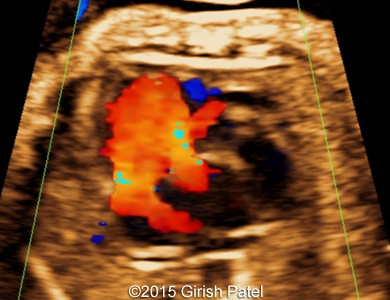

Following images and videos show a case of double inlet left ventricle with transposition of the great arteries that was seen at 26 and 36 weeks of otherwise non-complicated pregnancy.

Images 1, 2, 3, and 4: 2D images showing transverse scan of the heart with double inlet left ventricle and transposition of the great arteries. Following structures can be seen: dominant enlarged left ventricle (LV); diminutive right ventricle (RV) connected to the left ventricle via small bulboventricular foramen; both, left atrium (LA), and right atrium (RA) open to the left ventricle via separate tricuspid and mitral valves; foramen ovale flap can be seen within the left atrium; enlarged pulmonary artery (PA) arises from the left ventricle; small part of the aorta (Ao) arising from the diminutive right ventricle can be also seen.

Images 5, 6, 7: 2D color Doppler images showing the heart with double inlet left ventricle and transposition of the great arteries. Image 5 shows filling of the left ventricle via separate mitral and tricuspid valves (doubled red flow). Images 6 and 7 shows parallel arrangement of the aorta and pulmonary artery (blue flows).